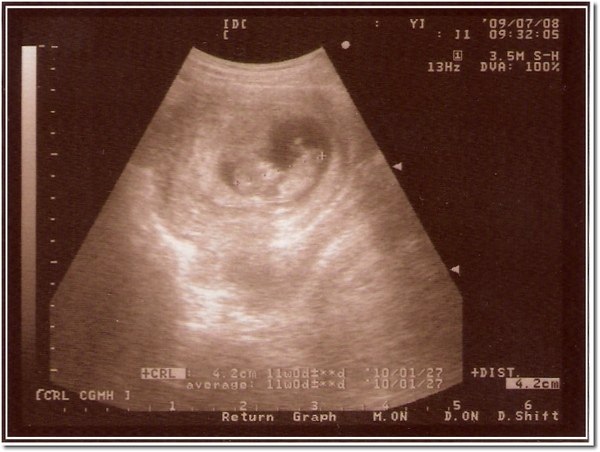

98/07/08 第三次超音波,第一次正式產檢,大約11週多

98070801.jpg

3ca8b998.gif 這次照超音波已經看得到雛型了唷~

還且還會像小蝦子一樣跳起來

第一次感覺到真的有一個小生命在肚子裡成型了

這感覺真的很奇妙